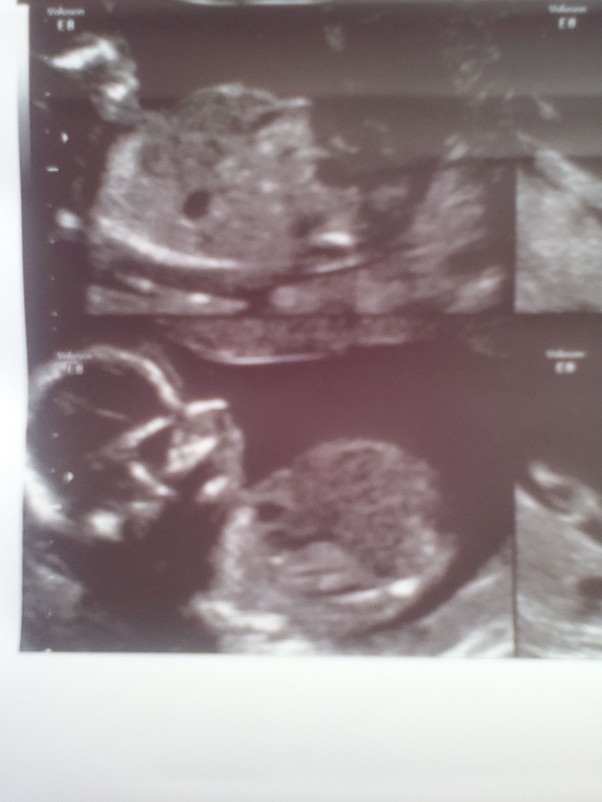

Moje malenstwo 31 tydzien :) dzidzius jest malym wstydzioszkiem bo mama nadal nie wie czy bedzie to chlopiec czy dziewczynka :)